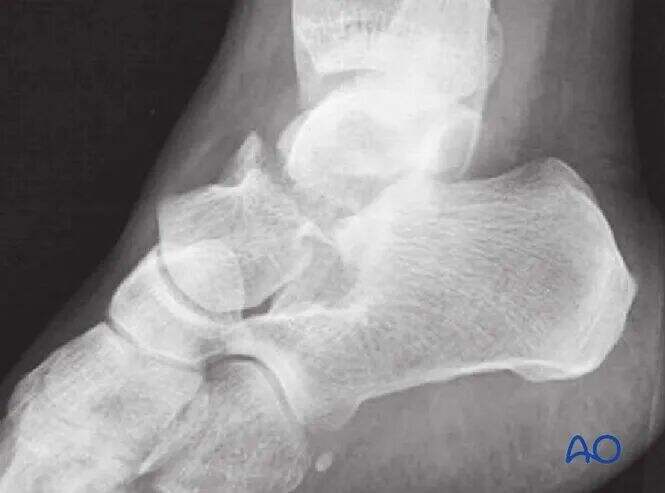

Nezamaknjeni zlomi morda zahtevajo le preproste rentgenske posnetke, vendar je ta primer redko; večina zlomov vratu talusa ima vsaj nekaj stopnje zamika.

CT slikanje je neprecenljivo, kadar obstaja dvom o premiku zloma ali kadar je potrebno odstraniti okostnico subtalarne sklepa. Pri hujših poškodbah običajno velja, da večji premik nakazuje hujšo osteohondralno poškodbo subtalarne in tibiotalarne sklepa. Takšni zlomi pogosto zahtevajo kirurško odstranitev okostnice in fiksacijo.